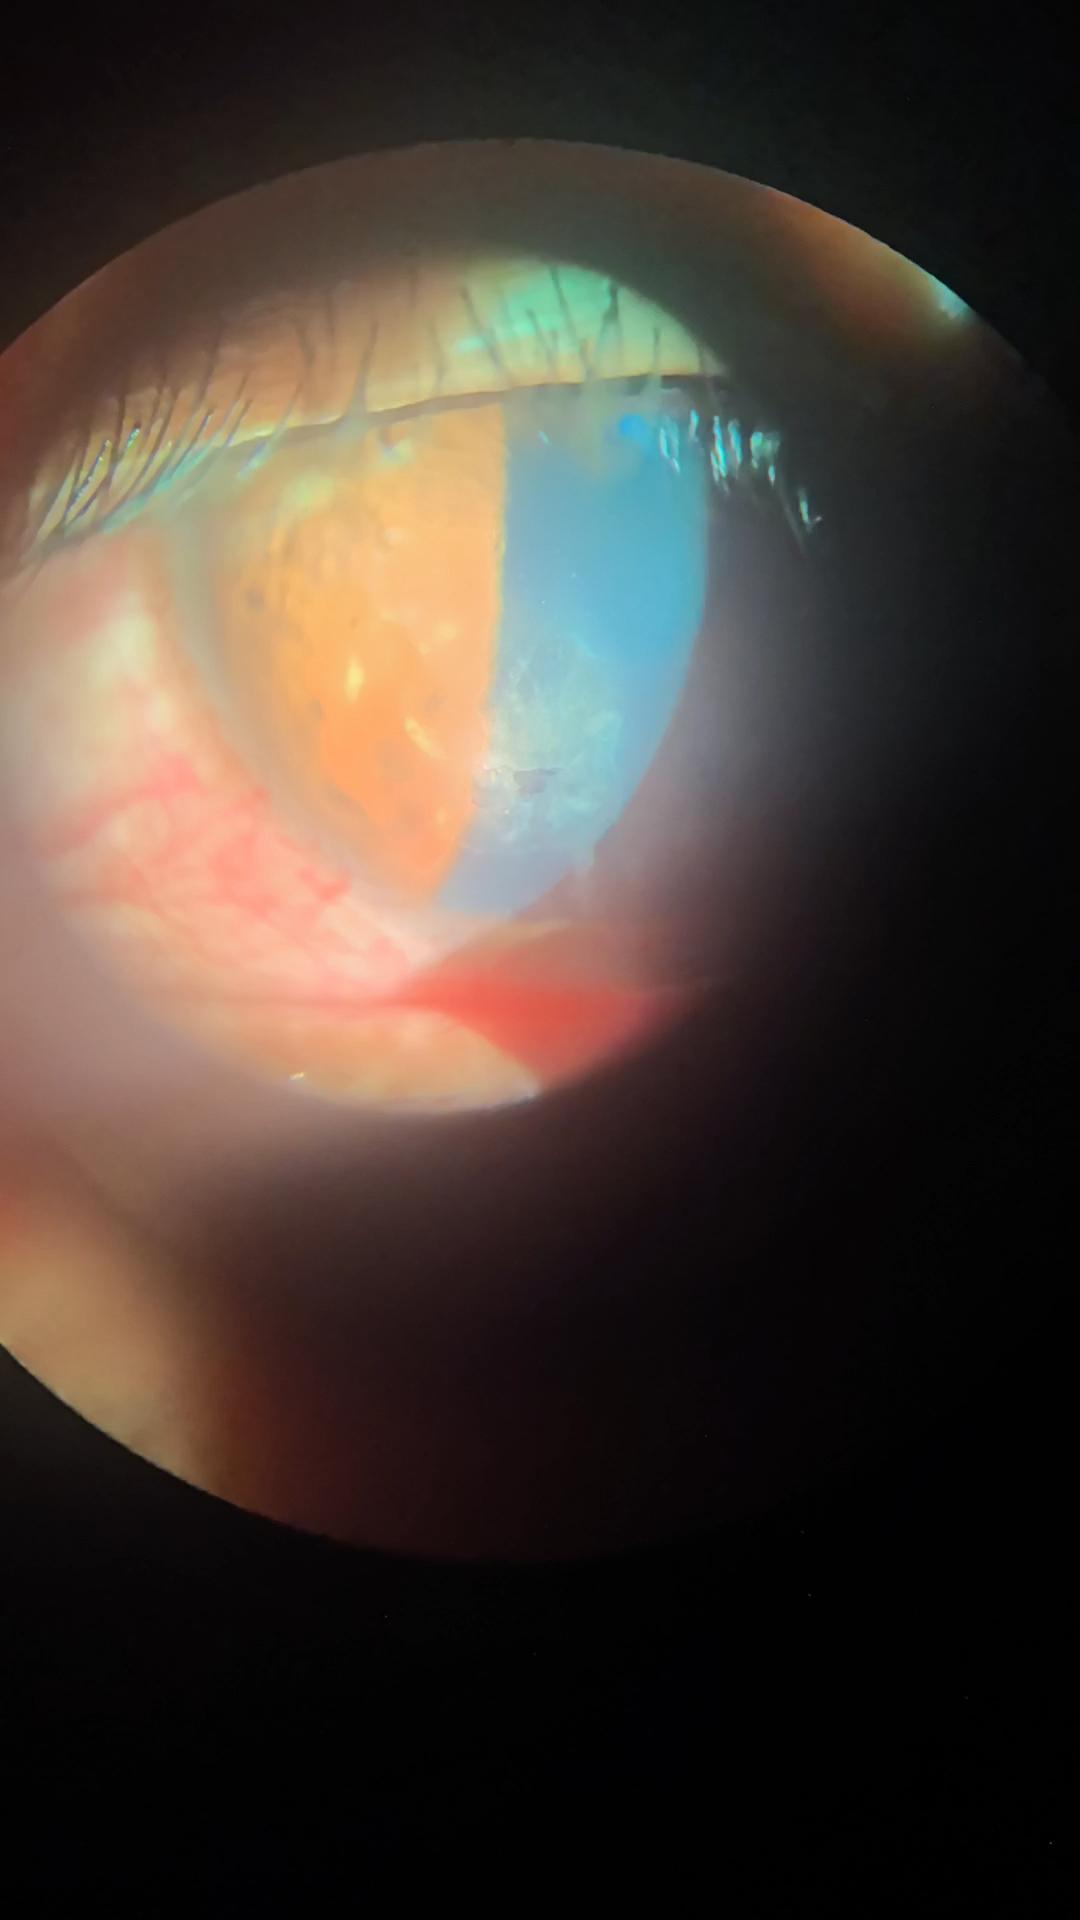

荧光素染色显示着色区(绿色)为角膜上皮糜烂